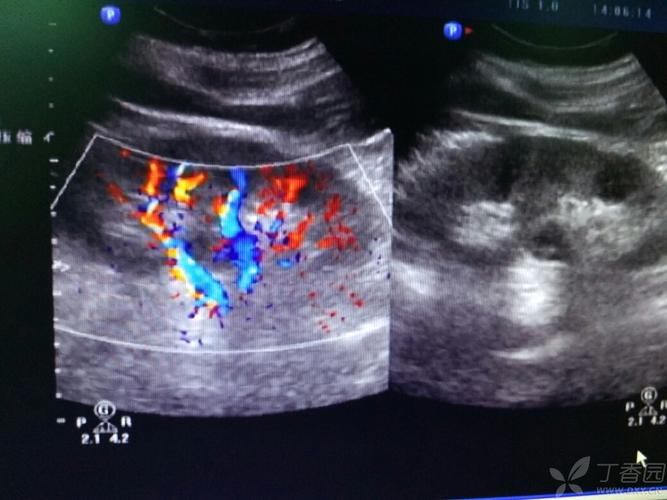

【贴图】双肾盂,双输尿管畸形

双肾盂图片

肾盂肾盏图片

肾盂分离图片

肾盂图片